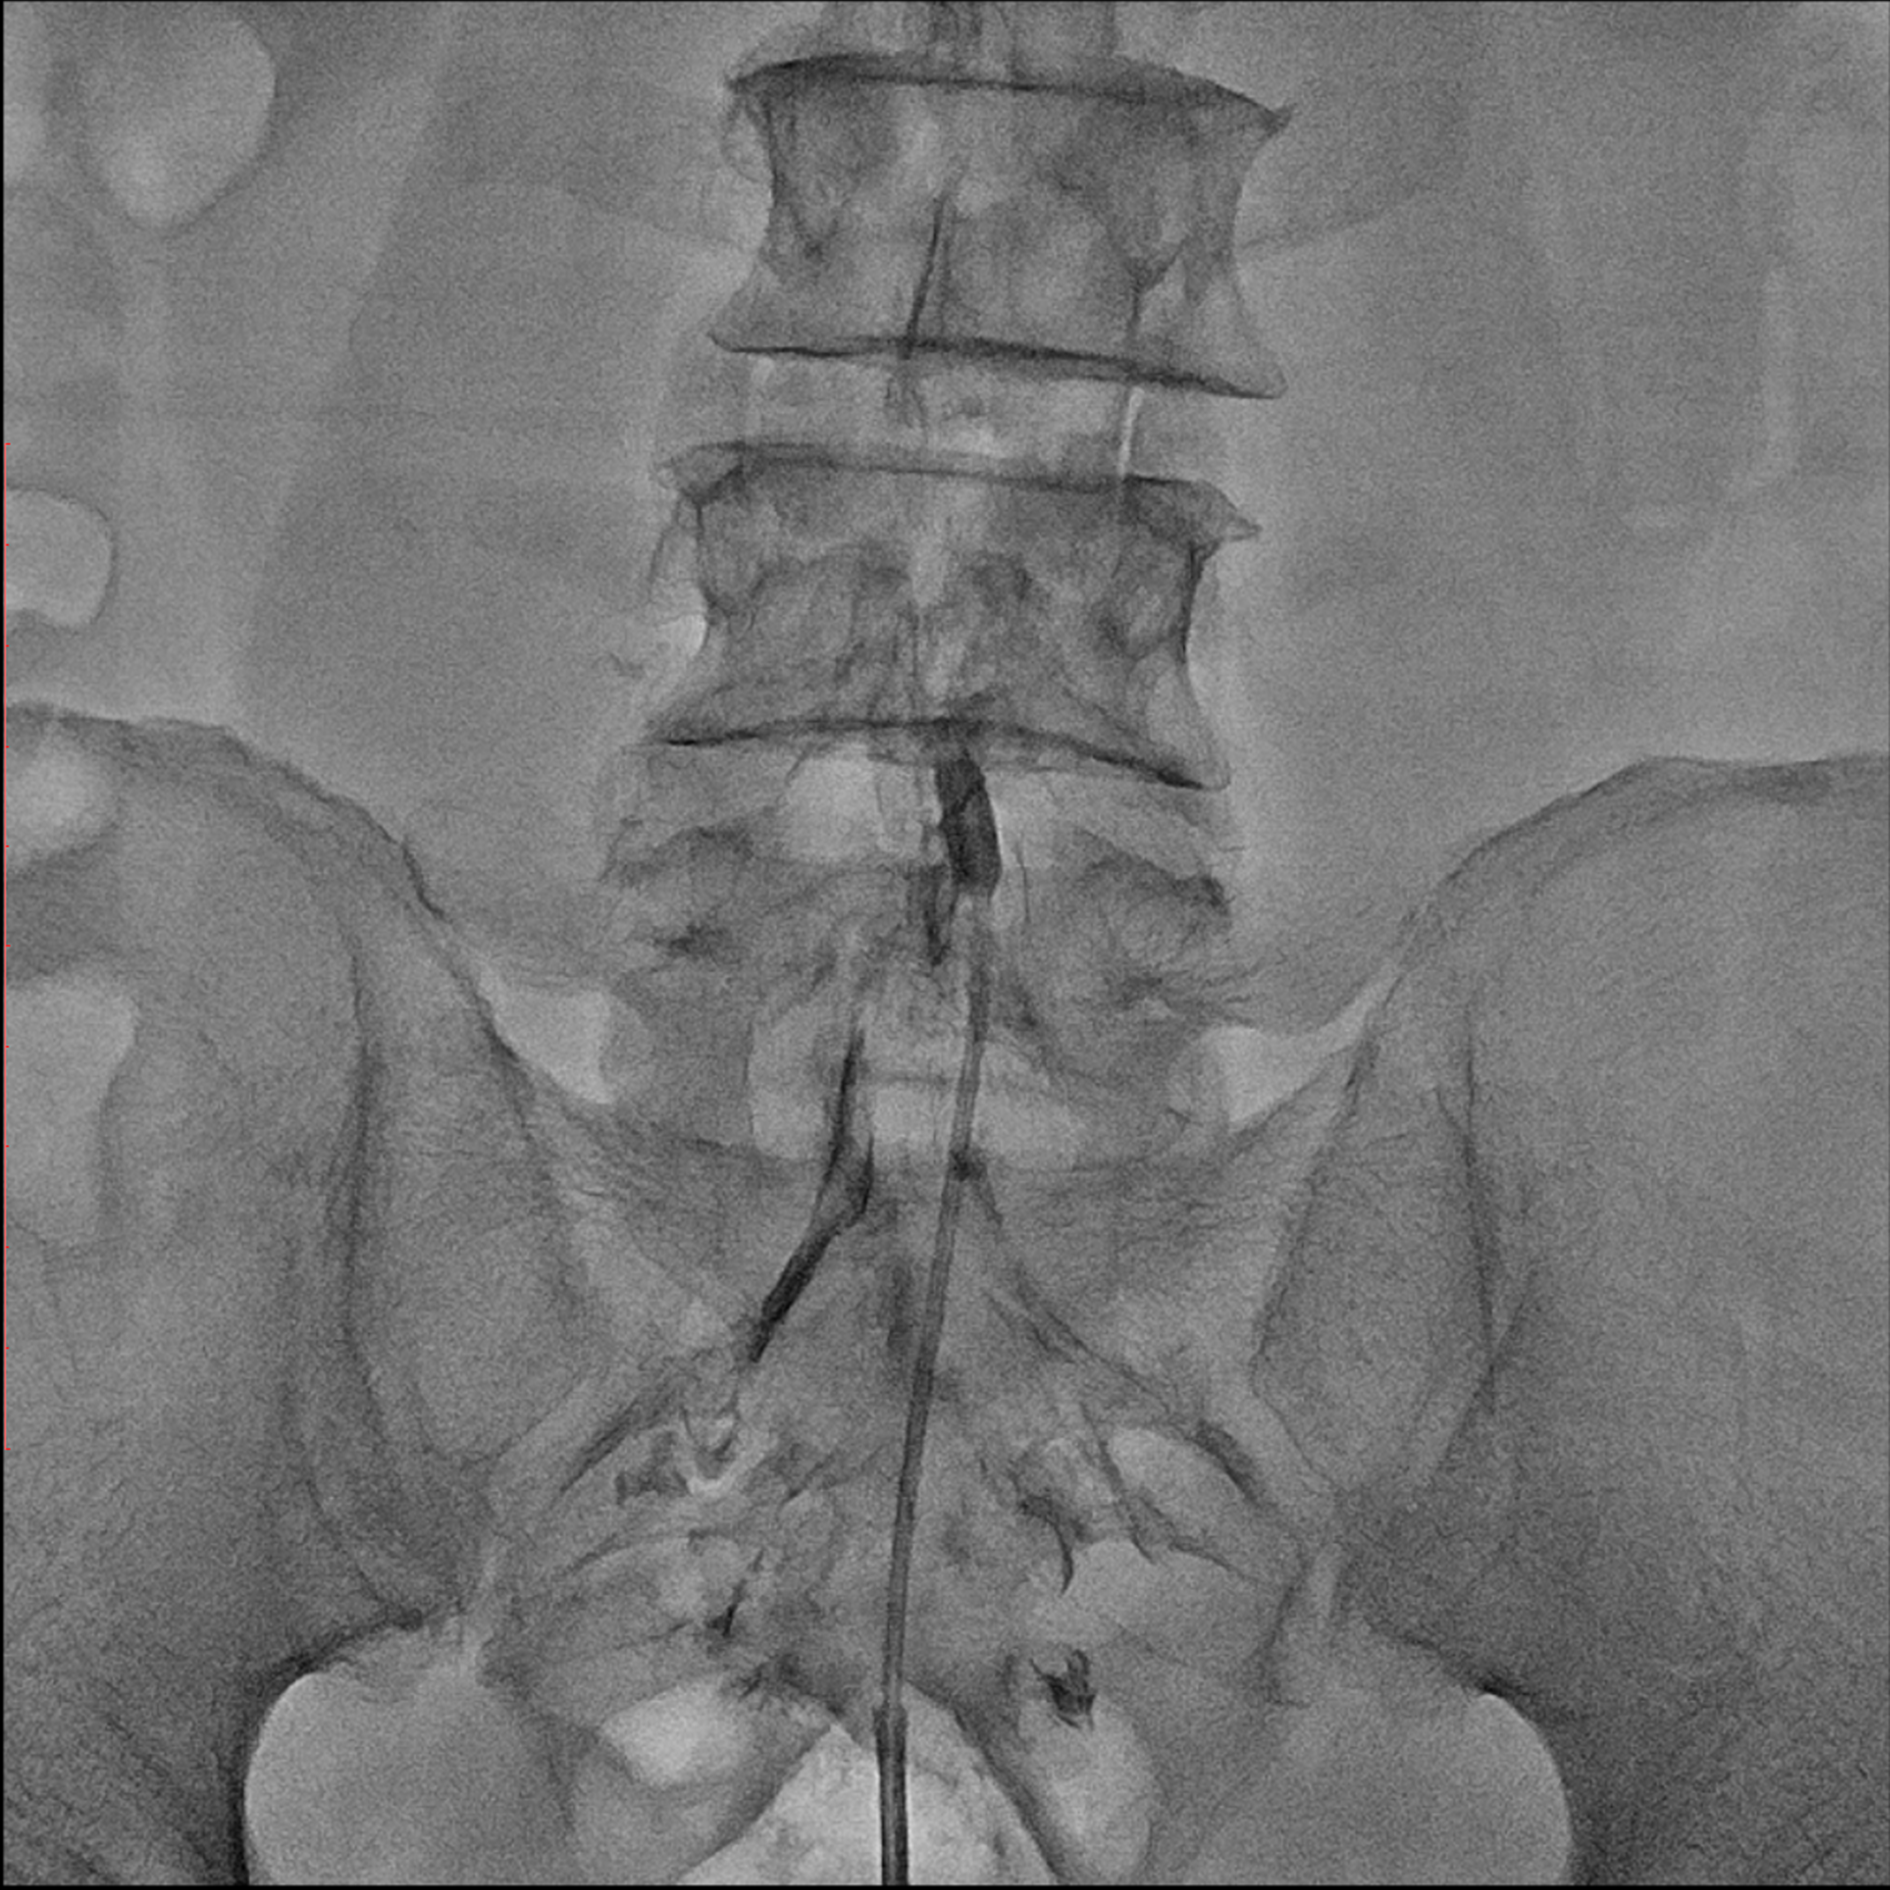

경막외 유착박리술, Epidural Neuroplasty